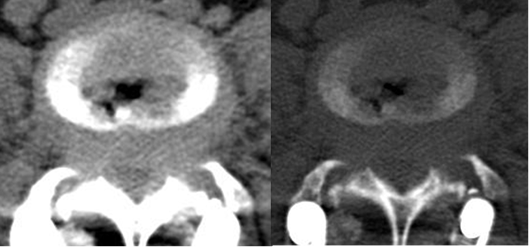

Fig 120. Laminectomía.

A: TAC axial en ventana de tejido y B: TAC axial en ventana osea. Disco degenerado con fenómeno del vacío y prominencia difusa. Cambios PostQx, con laminectomía derecha.